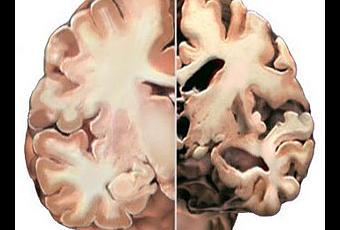

Aunque el origen de la EA no es bien conocido, las lesiones cerebrales que caracterizan el diagnòstico de enfermedad de alzheimer se producen por el acùmulo de una proteìna denominada beta amiloide (Ab) procedente de una anormal proteolìsis (fragmentaciòn) de una proteìna precursora amiloide (PPA) localizada en las neuronas, y tras su expulsiòn de las cèlulas en forma de fibrillas se deposita en el cerebro o en sus vasos sanguìneos, formando lo que se conoce como placas seniles o placas neurìticas, observadas por primera vez por Alois Alzheimer en el año 1907. A esta lesióòn se suma la producida por otra proteìna denominada tau cuya anormal agregaciòn en forma de ovillo (ovillos neurofibrilares) de localizaciòn intraneuronal lleva consigo la destrucciòn de las neurona, estando la evoluciòn de la EA en relaciòn con el nùmero de neuronas destruidas. Estos depòsitos de proteìnas son el resultado de un desorden biològico en la producciòn y eliminaciòn por aclaramiento o limpieza cerebral de estas formaciones como consecuencia de un fallo de dos mecanismos ìntimamente relacionados: el glutatiòn y el mecanismo de la proteolìsis.